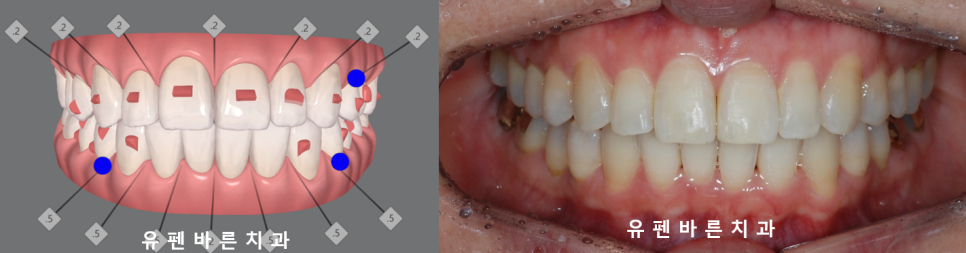

28개의 인비절라인라이트 옵션으로

유지장치까지 새롭게 깔끔히 부착되고

마무리된 모습인데요

결과적으로

앞니끼리 닿지 않아

앞니에 외상을 없애주고

양쪽 어금니가 맞물리게 되면서

식사도 잘 하실 수 있게 되어

2주마다 장치교체, 치료기간 1년3개월

윗니가 아랫니를 약간 덮으면서

바르게 정상교합이 된 모습을

보실수 있는데요.

클린체크의 예상대로

교정이 마무리된

사진을

확인해보실 수 있습니다.